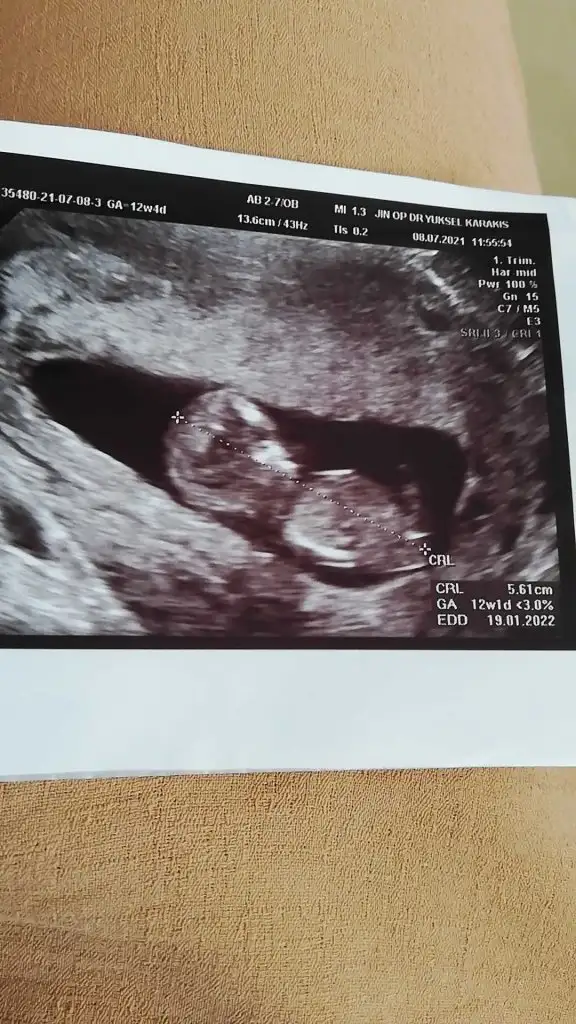

Kaç haftalık USG 11 12 13 haftalar olmalı nub görünmüyor başka USG varsa paylaşın

Kız görünüyor11+2 bı tahminde bulunur musun canım Eki Görüntüle 2894305

Kaç haftalık USG 11 12 13 haftalar olmalı nub görünmüyor başka USG varsa